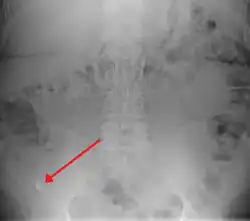

| A fecalith marked by the arrow which has resulted in acute appendicitis. | |

Appendicolith as seen on plain X ray